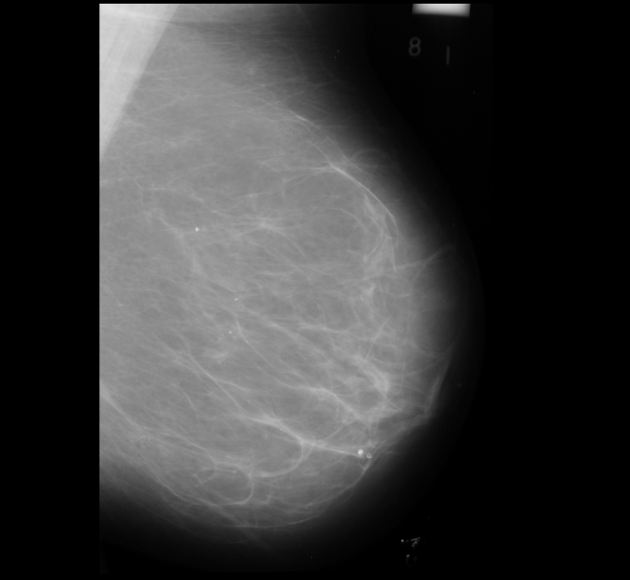

Neural networks require a large number of images as input for the training purposes. Because of limited resources of large dataset availability, the dataset used for this research is mini MIAS dataset [10]. It comprises of total 322 images which are further divided into a number of classes. Original size of each image in the dataset is 10241024. Sample images are shown in Figure 1.

3 Dataset